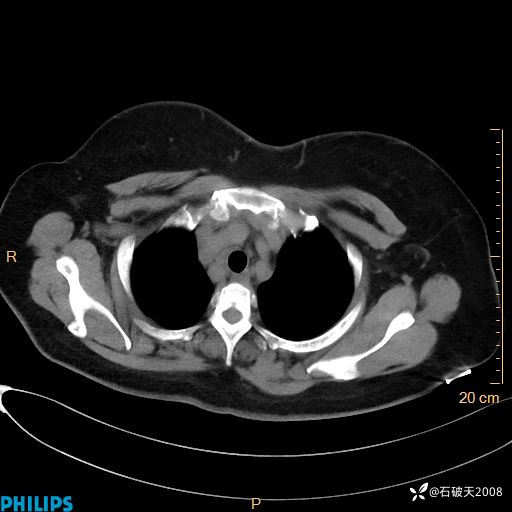

肺结节病?纵膈型肺癌?淋巴瘤?有点意思,欢迎围观

女 52岁 主 诉:咳嗽10余天,咳痰2天。

现病史:10余天前无明显诱因出现咳嗽,呈阵发性干咳,伴咽喉部发痒,无咽痛,无咳痰,无鼻塞、流涕、打喷嚏,无发热、畏寒、寒颤,无头痛、头晕,无胸闷、胸痛,无反酸、烧心,无腹痛、腹泻,无尿频、尿急,无皮疹等,在当地诊所求治,给予口服药物治疗(具体不详),病情无好转。遂在当地社区卫生服务中心开具口服药物治疗(具体不详),疗效欠佳。2天前出现咳痰,在我院门诊求治,行胸部CT提示肺部感染,建议住院,患者要求口服药物治疗,目前仍咳嗽、咳白色粘痰,白天量多,夜间自觉喉部喘鸣音,遂再次来院就诊,以“肺部感染”为诊断收入院。发病以来,神志清,精神可,饮食可,夜间睡眠差,大小便正常,近期体重无明显变化。

静脉期